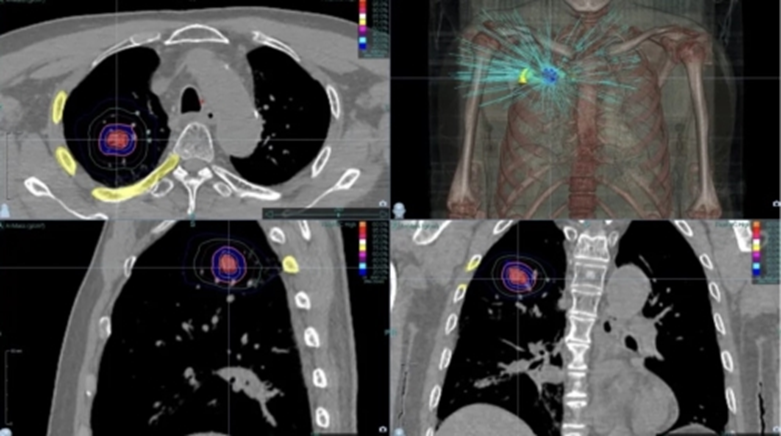

The patient underwent one treatment course, receiving 11 Gy per session for a total of five sessions (11 Gy × 5 fractions).

- CyberKnife Care Plan

- Prescription dose: 11 Gy × 5F

- Prescription isodose line: 63%

Radiation Therapy Plan:

After just five treatment sessions, the patient showed significant clinical improvement. A follow-up one month after radiotherapy revealed that the original lung lesions had completely disappeared.